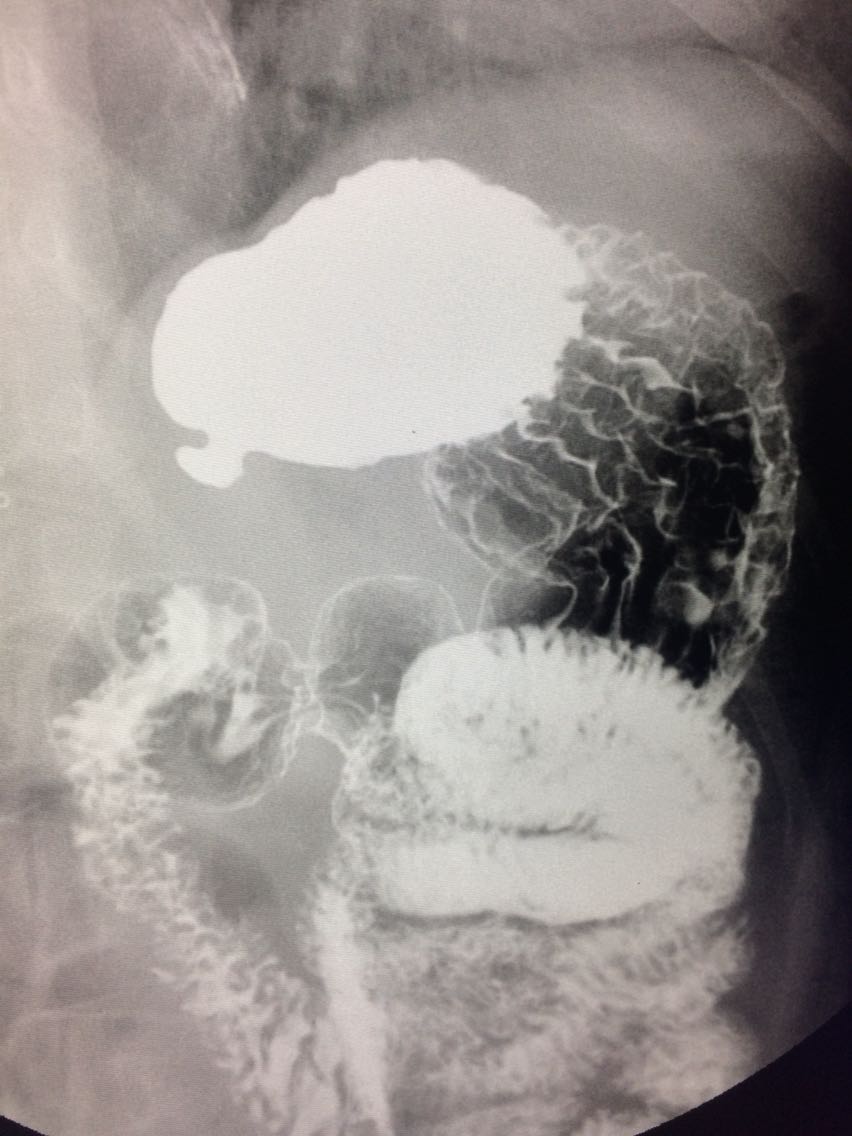

胃底憩室一例

女.47岁 体检来诊。 平素体健,无明显症状。 做上消化道造影如图。

诊断,胃底憩室。 治疗,患者无明显症状,未予治疗。